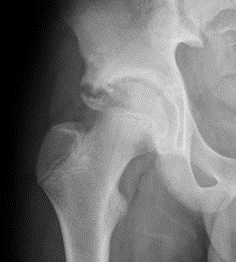

AIIS Avulsion

AIIS avulsion 1AIIS avulsion 2AIIS avulsion 3

Attachment

Rectus femoris